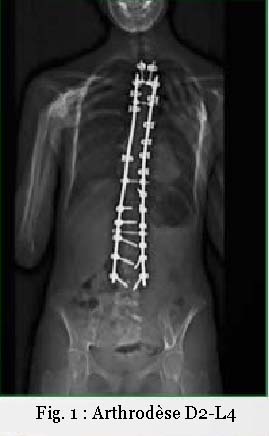

Les enfants ont souvent eu nombre d’examens complémentaires, et parfois, d’autres examens s’imposent. À la lecture de l’imagerie médicale, il n’est pas rare de trouver une anomalie rachidienne non objectivée précédemment (fig. l et 2).

Les douleurs post-interventions sur scoliose [5,6] demandent un ajustement particulier, le rachis ayant été rigidifié par l’arthrodèse, par exemple T2-L4, les zones mobiles sont réduites. L’ostéopathe va détendre les contractures musculaires mais aussi les adhérences cicatricielles afin de retrouver une souplesse tissulaire.